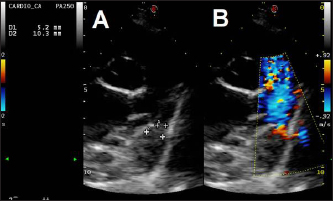

Thoracic radiographs showed left-sided cardiomegaly and pulmonary over circulation (Fig. 1). A transthoracic echocardiogram revealed severe left atrial and left ventricular dilation: left atrium/aorta (LA:Ao): 2.04, reference value: <1.6, normalized left ventricular internal diastolic diameter (LVIDDN): 3.02, reference value: ≤1.7) and large PDA, with an approximate minimal ostium and ampulla diameters of 5.2 and 10.3 mm (Fig. 2). Doppler echocardiography confirmed left-to-right flow across the PDA with a pressure gradient of 102 mmHg in systole and 41 mmHg in diastole. Mild mitral regurgitation was also noted.

Fig. 2. Transthoracic echocardiographic (right parasternal short axis view, optimized for duct visualization). (A) PDA visualization and its measurement and (B) left to right flow on CFM Doppler (dual mode).